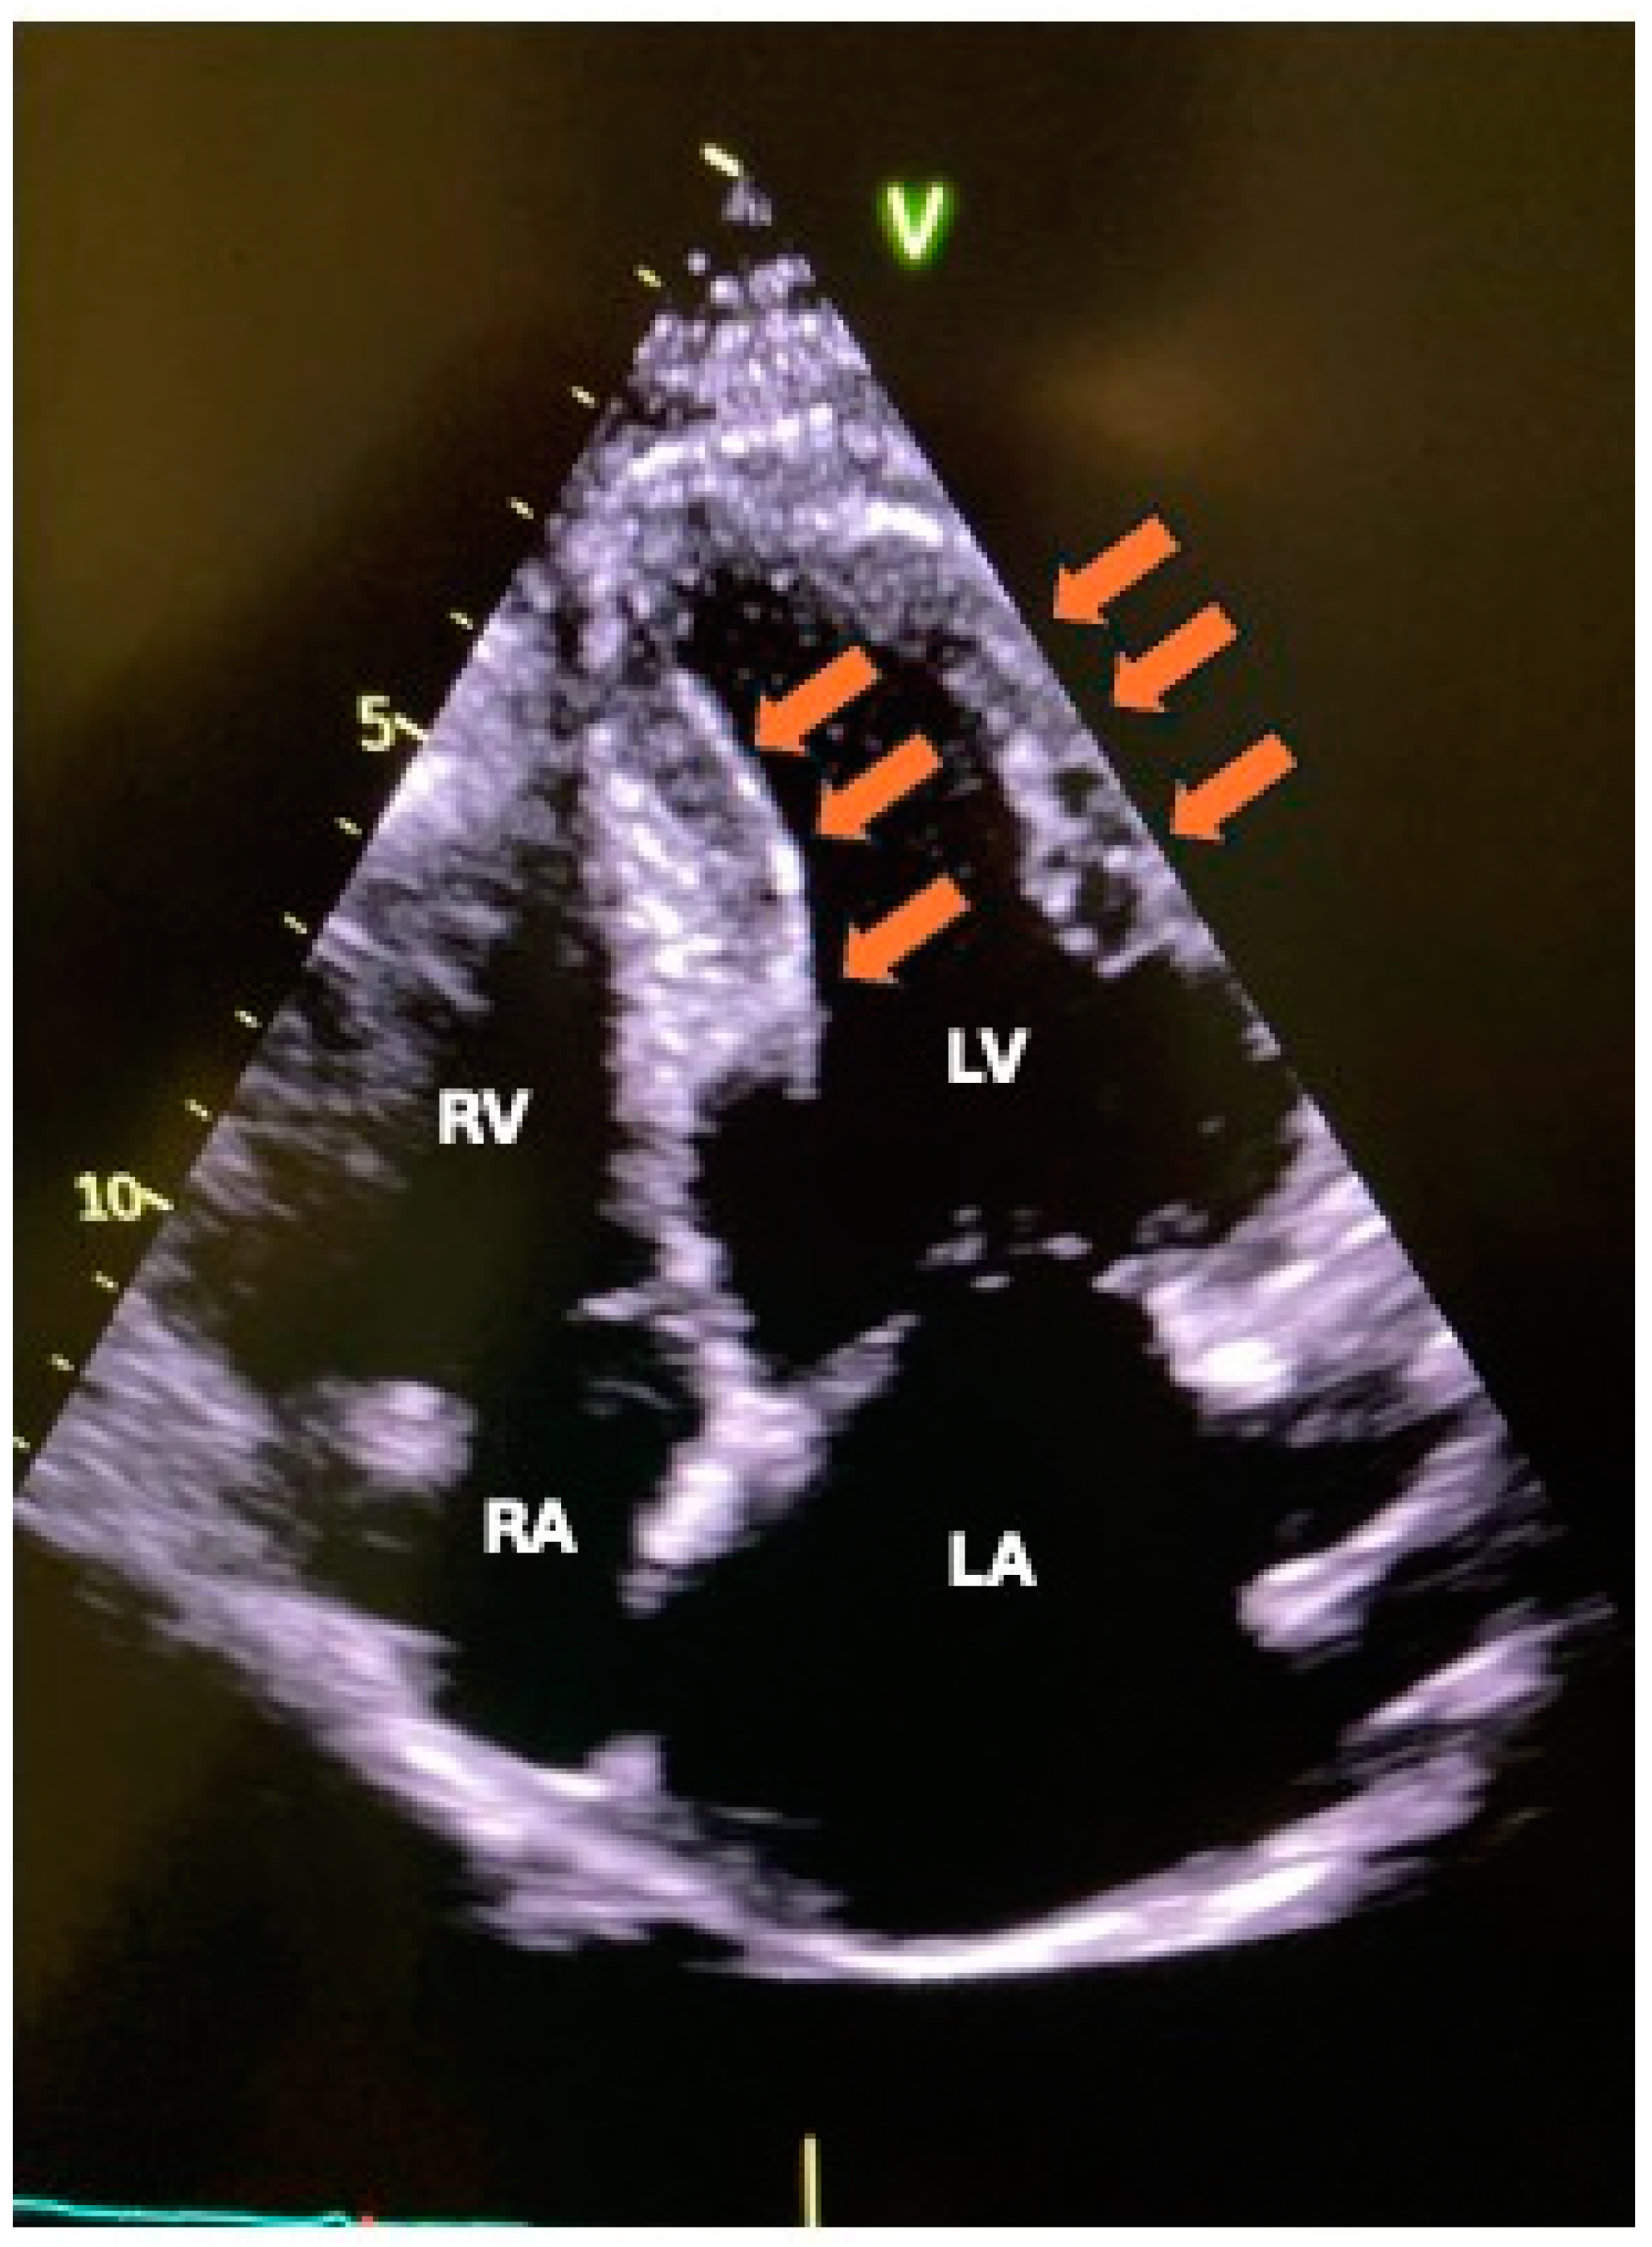

- L’Angiocola, P.; Donati, R. Cardiac masses in echocardiography: A pragmatic review. J. Cardiovasc. Echography 2020, 30, 5–14. (In English) [Google Scholar] [CrossRef]

- Aggeli, C.; Dimitroglou, Y.; Raftopoulos, L.; Sarri, G.; Mavrogeni, S.; Wong, J.; Tsiamis, E.; Tsioufis, C. Cardiac Masses: The Role of Cardiovascular Imaging in the Differential Diagnosis. Diagnostics 2020, 10, 1088. (In English) [Google Scholar] [CrossRef] [PubMed]

- Xia, H.; Gan, L.; Jiang, Y.; Tang, Q.; Zhang, P.; Tang, X.; Wen, L.; Liu, Z.; Gao, Y. Use of transesophageal echocardiography and contrast echocardiography in the evaluation of cardiac masses. Int. J. Cardiol. 2017, 236, 466–472. (In English) [Google Scholar] [CrossRef]